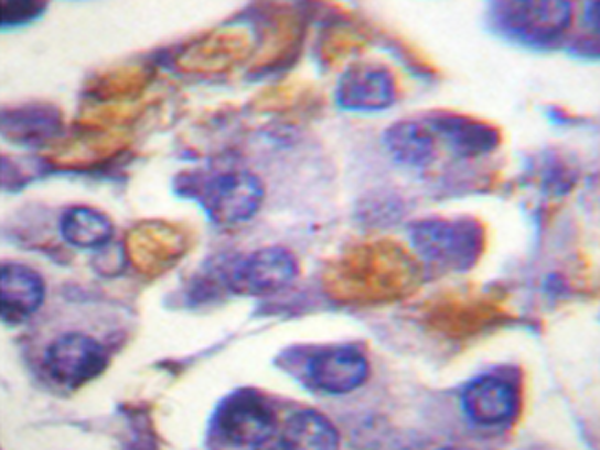

IHC positive control:

Human pancreas tissue

IHC Recommend dilution:

50-100